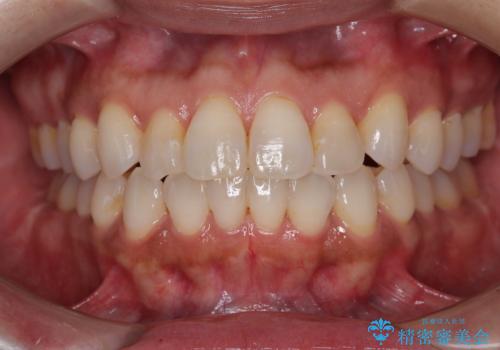

[マウスピース矯正] 海外留学中でも可能な矯正治療

担当医 大元洋佑